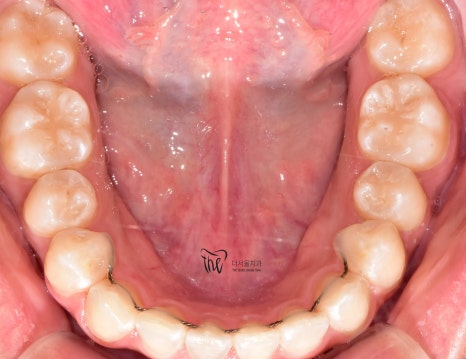

치아교정 후

다시 틀어지지 않도록

고정식 유지장치를 붙여드렸습니다.

앞니 안쪽면에

가느다란 철사를 붙이는 방식으로

치아들이 다시 흐트러지는 것을

예방하는 역할을 하게 됩니다.

다만, 철사가 탈락하면 다시 틀어질 수 있기 때문에

빠른 시일내에 치과로 내원하는 게 좋습니다.